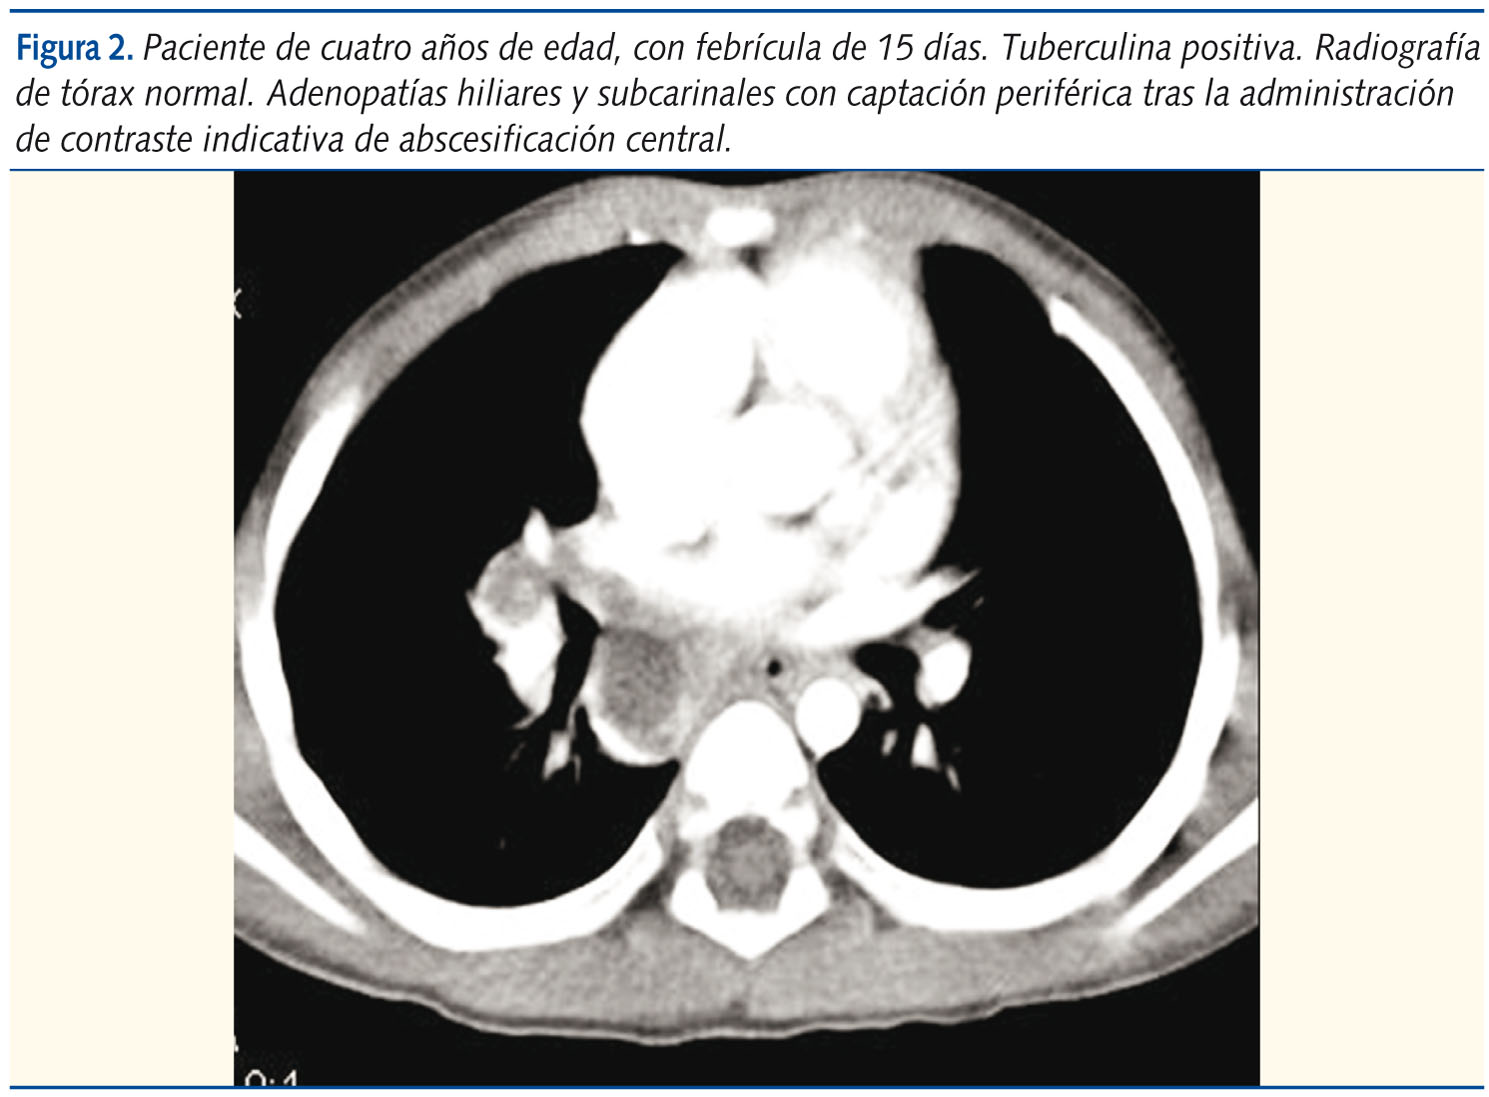

El diagnóstico de enfermedad tuberculosa se sustenta en: constatación de entorno bacilífero y prueba de tuberculina positiva, que significan infección, y detección por imagen de adenopatías mediastínicas, que traduce extensión y, por tanto, enfermedad. Por ello, la radiología es crucial. De entrada, en un determinado número de pacientes, sobre todo en los casos Índice, la radiografía muestra las adenopatías mediastínicas (la proyección lateral es extraordinariamente útil para la identificación de las adenopatías mediastínicas subcarinales, muy frecuentes). El estudio radiológico ha finalizado.

Pero si la radiografía simple es negativa o dudosa, la TC muestra extraordinaria sensibilidad para la detección y caracterización de las adenopatías13-16 (hasta un 60%). No obstante, hay una controversia reciente basada en el predominio, en algunas series, de captación homogénea tras la administración de contraste, lo que indicaría ausencia de caseificación y un carácter únicamente reactivo, más próximo a la primoinfección17,18. No es, sin embargo, nuestra experiencia (figura 2).